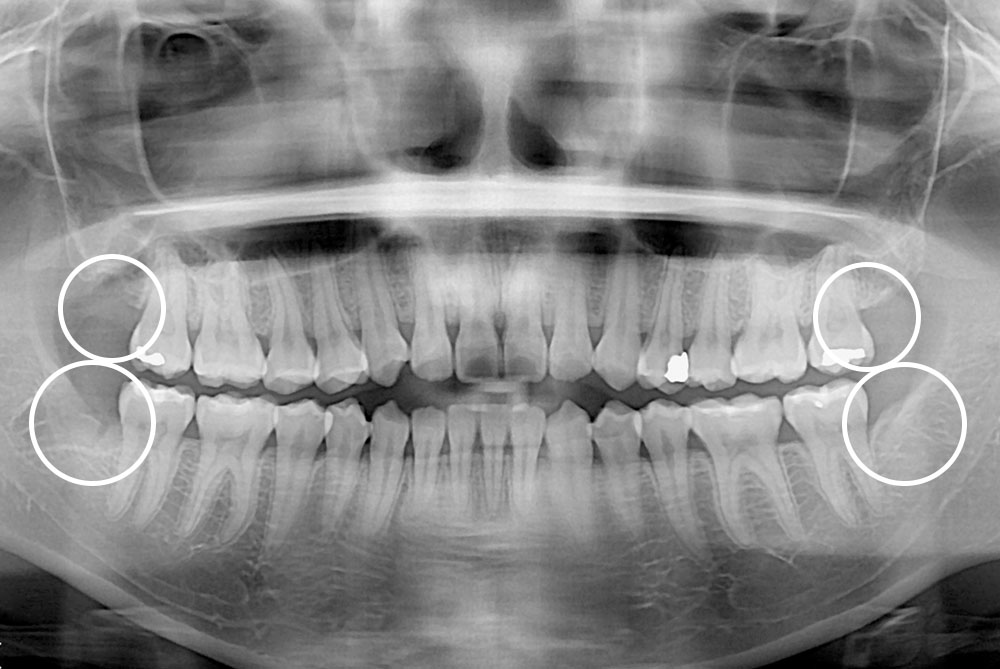

[사랑니] 매복 사랑니 발치

치료전 : 2017-06-30